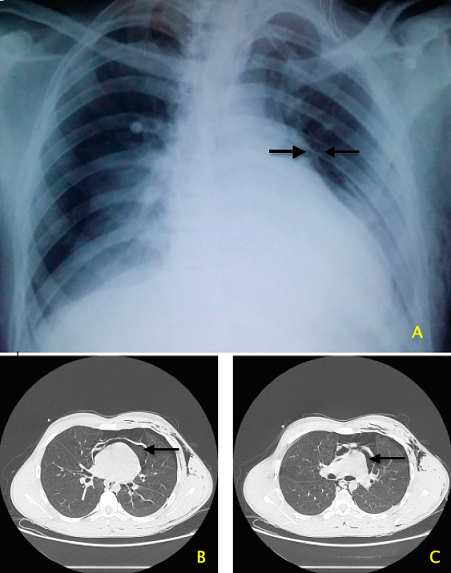

Il n'existe que peu d'études consacrées aux accidents d'équitation. Avec une incidence de 36/100000 pratiquants, et un taux de mortalité de 0.06/100000, la prévalence dans la population générale reste faible, mais la gravité de ces accidents est liée à leur violence. Nous rapportons le cas d'un patient de 17 ans, victime d'un traumatisme thoraco-abdominal par coup de sabot. Reçu en état de choc aux urgences, avec une sensibilité abdominale, des sueurs profuses, des conjonctives décolorées, une tachycardie à 120bpm, et une tension artérielle à 80/50 mmHg. Le bilan lésionnel après stabilisation objectivait au niveau thoracique: un important emphysème sous cutané, un pneumothorax gauche, un pneumomediastin et une solution de continuité de la face antérieure du péricarde avec pneumopéricarde, et au niveau abdominal: un éclatement de la rate avec un hématome périsplénique et un épanchement intrapéritonéal de grande abondance. Le patient est admis au service de Réanimation après drainage thoracique et splénectomie d'hémostase réalisée en urgence. Le drainage pleural simple a permis le drainage pleural.